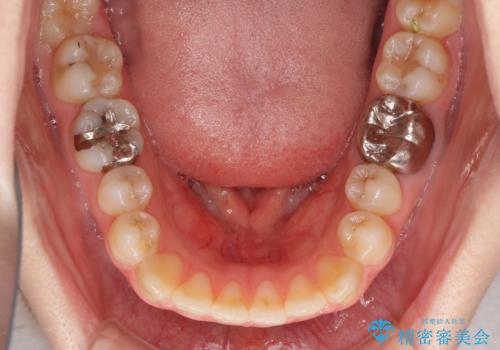

- 口元の膨らみが気になるとのことで来院された患者様です。

非抜歯で口元の突出感を少し改善させる治療も提案しましたが、最大限口元を引っ込めたいとのことでした。

上下左右第一小臼歯4本を抜歯し、ワイヤー装置により矯正治療を行うこととしました。